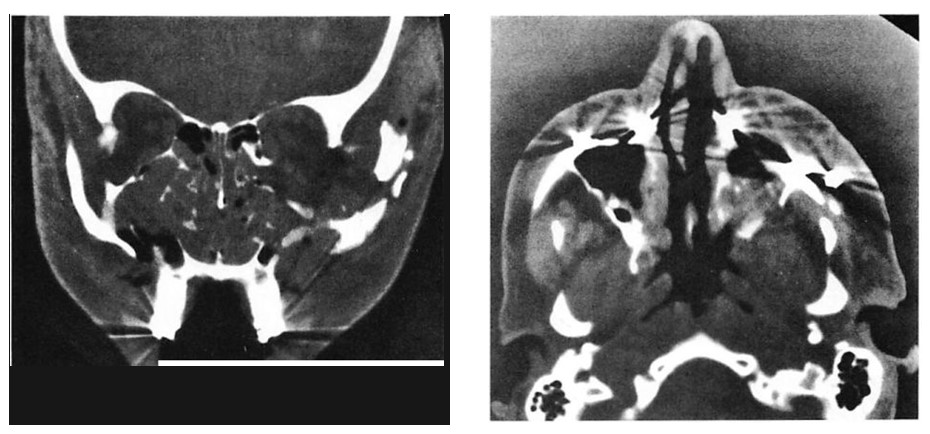

Fig 8. Comminuted nasoethmoid orbital and Le Fort fractures managed in a multiply injured 82-year-old woman. (No internal orbit reconstruction was performed.) (A) Preoperative axial computed tomographic (CT) scan. (B) Preoperative coronal reconstruction shows displacement of medial orbital walls. (Cervical-spine injuries precluded positioning for coronal scan.) (C) Postoperative coronal view (reconstructed) at 4 weeks shoivs stable reduction of medial orbital walls. (D) Postoperative plain film shows fixation used. (E) Clinical result 6 months postoperatively.

Fig 8. Comminuted nasoethmoid orbital and Le Fort fractures managed in a multiply injured 82-year-old woman. (No internal orbit reconstruction was performed.) (A) Preoperative axial computed tomographic (CT) scan. (B) Preoperative coronal reconstruction shows displacement of medial orbital walls. (Cervical-spine injuries precluded positioning for coronal scan.) (C) Postoperative coronal view (reconstructed) at 4 weeks shoivs stable reduction of medial orbital walls. (D) Postoperative plain film shows fixation used. (E) Clinical result 6 months postoperatively.

Fig 9. Computed tomographic (CT) scans of patient who suffered low-energy Le Fort II and III fractures treated with miniplates at the Le Fort I level and microplates along the infraorbital rims. (A) Preoperative CT shows pronounced impaction of central midface. (B) Axial scan through infraorbital rim shows anatomical reduction 3 days postoperatively. (C) CT scan at I year at similar cut shows unchanged position of bone fragments after healing.